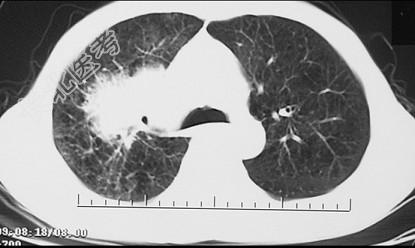

- 单项选择题男,68岁, 右侧胸痛伴右上臂麻木1周,胸部CT、MRI扫描如图, 最可能的诊断为 ( )

A、右上肺硬化性血管瘤

B、右上肺肉瘤并纵隔淋巴转移

C、右上肺不张

D、右上肺中央型肺癌并右上肺不张,纵隔淋巴转移

E、右上肺周围型肺癌并纵隔淋巴转移